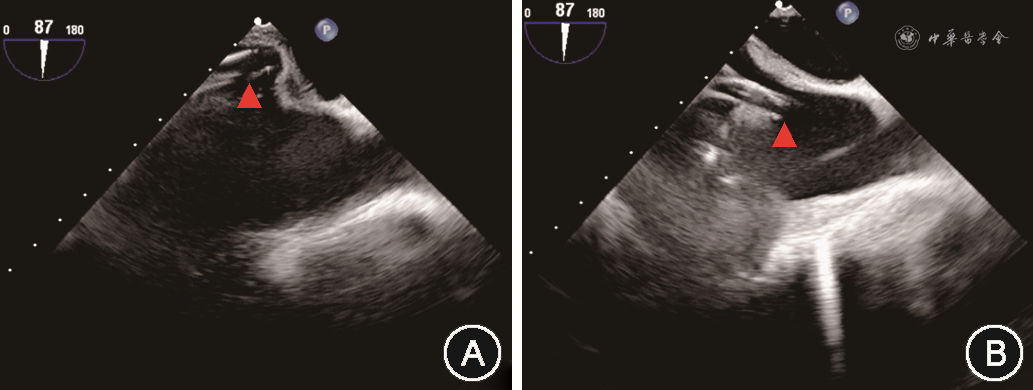

经导管三尖瓣缘对缘修复手术在全身麻醉、气管插管下进行。本研究所使用的经导管三尖瓣缘对缘修复器械为淇麟三尖瓣缘对缘修复系统(上海申淇医疗科技有限公司)、Neoblazar经导管三尖瓣夹合器及输送系统(江苏臻亿医疗科技有限公司)。本文所描述的手术过程以淇麟三尖瓣缘对缘修复系统为例。经右侧股静脉穿刺送入加硬导丝,在TEE 双腔切面引导下将导丝送入上腔静脉。使用18 Fr(1 Fr=0.33 mm)扩张子扩张股静脉穿刺处。将导引鞘头端调直,在TEE Bicaval View引导下沿导丝送入导引鞘使其头端位于右心房中部。若导引鞘头端朝向房间隔,可通过向L方向旋转S/L旋钮,或调整导引鞘+/-旋钮增加头端弯度并逆时针旋转导引鞘,使导引鞘头端远离房间隔(图1)。在体外预先测量导引鞘和夹子输送系统的位置关系,并在夹子输送系统上做标记。将夹子输送系统从导引鞘中送入右心房,在TEE双腔切面引导下送入标记深度,完成导引鞘和输送系统的对位,使夹子头端位于右心房中部。TEE显示右心室流入道/流出道切面及Biplane切面(图2),向F方向旋转夹子输送系统上F/E旋钮,使夹子朝向三尖瓣(图3)。通过旋转导引鞘、调整导引鞘S/L旋钮和输送系统F/E旋钮,使输送系统头端运动轨迹在上述两个TEE切面上都和三尖瓣水平垂直。若夹子输送系统从间隔斜向三尖瓣时,被称为“间隔拥抱”(Septal Hugger)现象(图4),可通过向L方向旋转S/L旋钮并顺时针旋转导引鞘调整。通过向患者头端推送或向脚端回撤整体系统,使夹子输送系统在TEE右心室流入道/流出道切面朝向反流束。打开夹子到120°,旋转夹子输送系统手柄使夹子在TEE经胃底短轴切面垂直于反流处瓣膜对合缘(图5)。关闭夹子,操作夹子输送系统手柄,将夹子送入右心室三尖瓣瓣下,切勿送入过深。打开夹子到120°,再次在TEE经胃底短轴切面确定夹子方向。顺时针旋转或逆时针旋转导引鞘,将使夹子分别靠近三尖瓣隔瓣或前(后)瓣,同时回撤夹子输送系统手柄,用夹子捕获三尖瓣隔瓣或前(后)瓣。通常使用TEE右心室流入道/流出道切面及Biplane切面来显示和引导捕获瓣叶,若此切面图像不能清晰显示夹子是否成功捕获瓣叶,可以通过TEE经胃底短轴切面显示瓣叶活动被夹子限制来判断夹子是否捕获瓣叶(图6)。确定夹子捕获瓣叶后,放下上夹壁(Gripper),缓慢关闭夹子,关闭夹子过程中可通过TEE经胃底短轴切面观察到瓣叶活动受限并随着夹子关闭隔瓣或前(后)瓣聚拢(视频1,TEE显示夹子关闭过程,请扫描文章首页二维码观看)。关闭夹子后,TEE检测三尖瓣反流情况,夹子夹持瓣叶长度,评估是否需要调整夹子位置或因夹持瓣叶长度不足而进行再次夹持,以及是否需要补充额外的夹子。评估满意后按照夹子释放流程释放夹子。

注:通过调整绿色方框和红色方框图像中的蓝线,使其分别和夹子臂和夹子输送系统重合,则可在蓝色方框中精确显示夹子和捕获瓣叶

因三尖瓣位于心脏的前方,距离食管较远,且容易受到左心人工瓣膜以及夹子输送系统的声影影响,经食管超声探头位于食管中下段时,有可能不能提供足够清晰的图像显示夹子捕获三尖瓣。将食管超声探头送到胃部,并将食管探头前屈并向患者右侧旋转,在20°~60°范围内调整产生的经胃底短轴切面,避免了左心或输送系统的声影影响,可在一个二维平面同时显示三尖瓣三个瓣叶的结构,在此切面使用Biplane功能,可获得显示三尖瓣前瓣和后瓣的右心室长轴图像,可以辅助判断夹子进入右心室的深度,但不能为夹子捕获瓣叶提供引导。利用经胃底短轴图像进行三维图像重建,再利用Multiview进行图像分割重建,可精准获得和夹子重合的超声切面,显示夹子和瓣叶的关系,可用于引导瓣叶捕获和判断捕获程度(图6)。但因进行Multiview图像重建后,图像清晰度会有明显下降,因此对于重建前的二维超声图像有较高的质量要求。因此,经胃底短轴切面在经导管三尖瓣缘对缘修复手术中诸如夹子位置和方向的调整、瓣叶捕获判断、瓣叶夹持程度的判断等重要步骤中发挥关键作用[20]。如右心严重扩大或存在心脏转位,食管中段切面和经胃底短轴切面均无法提供满足引导要求的图像时,可使用心腔内超声[21]。